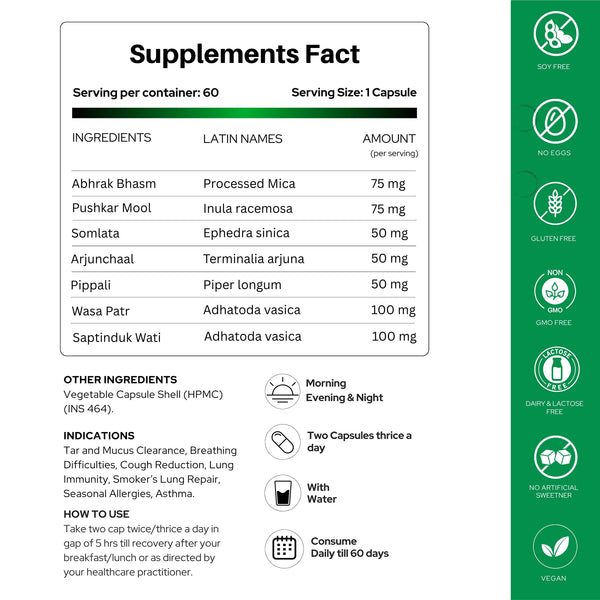

खुराक और उपयोग

उपयोग विधि: पूर्णतः ठीक होने तक, या अपने चिकित्सक के निर्देशानुसार, नाश्ते/दोपहर के भोजन के बाद, दिन में दो या तीन बार (प्रत्येक 5 घंटे में) दो कैप्सूल लें।- सावधानी: यदि आप गर्भवती हैं, स्तनपान करा रही हैं, या श्वसन संबंधी दवाइयां ले रही हैं तो अपने चिकित्सक से परामर्श करें (कुछ जड़ी-बूटियां परस्पर क्रिया कर सकती हैं या प्रतिरक्षा को प्रभावित कर सकती हैं)।

मुख्य सामग्री

- भृंगराज (एक्लिप्टा अल्बा): फेफड़ों की सूजन को कम करता है, बलगम को साफ करता है, फेफड़ों के ऊतकों की रक्षा करता है।

- मुलेठी (ग्लाइसीर्रिजा ग्लबरा): कफ निस्सारक; बलगम को ढीला करता है, श्वास नलिका को आराम देता है, खांसी को कम करता है।

- कांत लौह (लौह आधारित कैल्क्स): रक्त ऑक्सीजन का समर्थन करता है, ऊतक मरम्मत में सहायता करता है।

- आवला (एम्ब्लिका ऑफिसिनेलिस): एंटीऑक्सीडेंट; प्रतिरक्षा को बढ़ाता है, विषाक्त पदार्थों को कम करता है।

- कपर्द भस्म (कौड़ी के खोल का छिलका): वायुमार्ग को मजबूत करता है, बलगम को साफ करता है, जलन को कम करता है।

- गिलोय (टीनोस्पोरा कॉर्डीफोलिया): एडाप्टोजेन; प्रतिरक्षा को बढ़ाता है, फेफड़ों को शुद्ध करता है, संक्रमण को कम करता है।

नीम (एजाडिरेक्टा इंडिका): रोगाणुरोधी, एलर्जीरोधी; संक्रमण को दूर करता है, एलर्जी को कम करता है।- तुलसी (ओसीमम सैंक्टम): कफ निस्सारक; कफ को साफ करती है, खांसी को शांत करती है, फेफड़ों के स्वास्थ्य को बढ़ाती है।

- सप्तपर्ण (एल्सटोनिया स्कॉलरिस): रक्त शुद्ध करता है, रक्तसंकुलता कम करता है, श्वसन क्रिया में सहायता करता है।